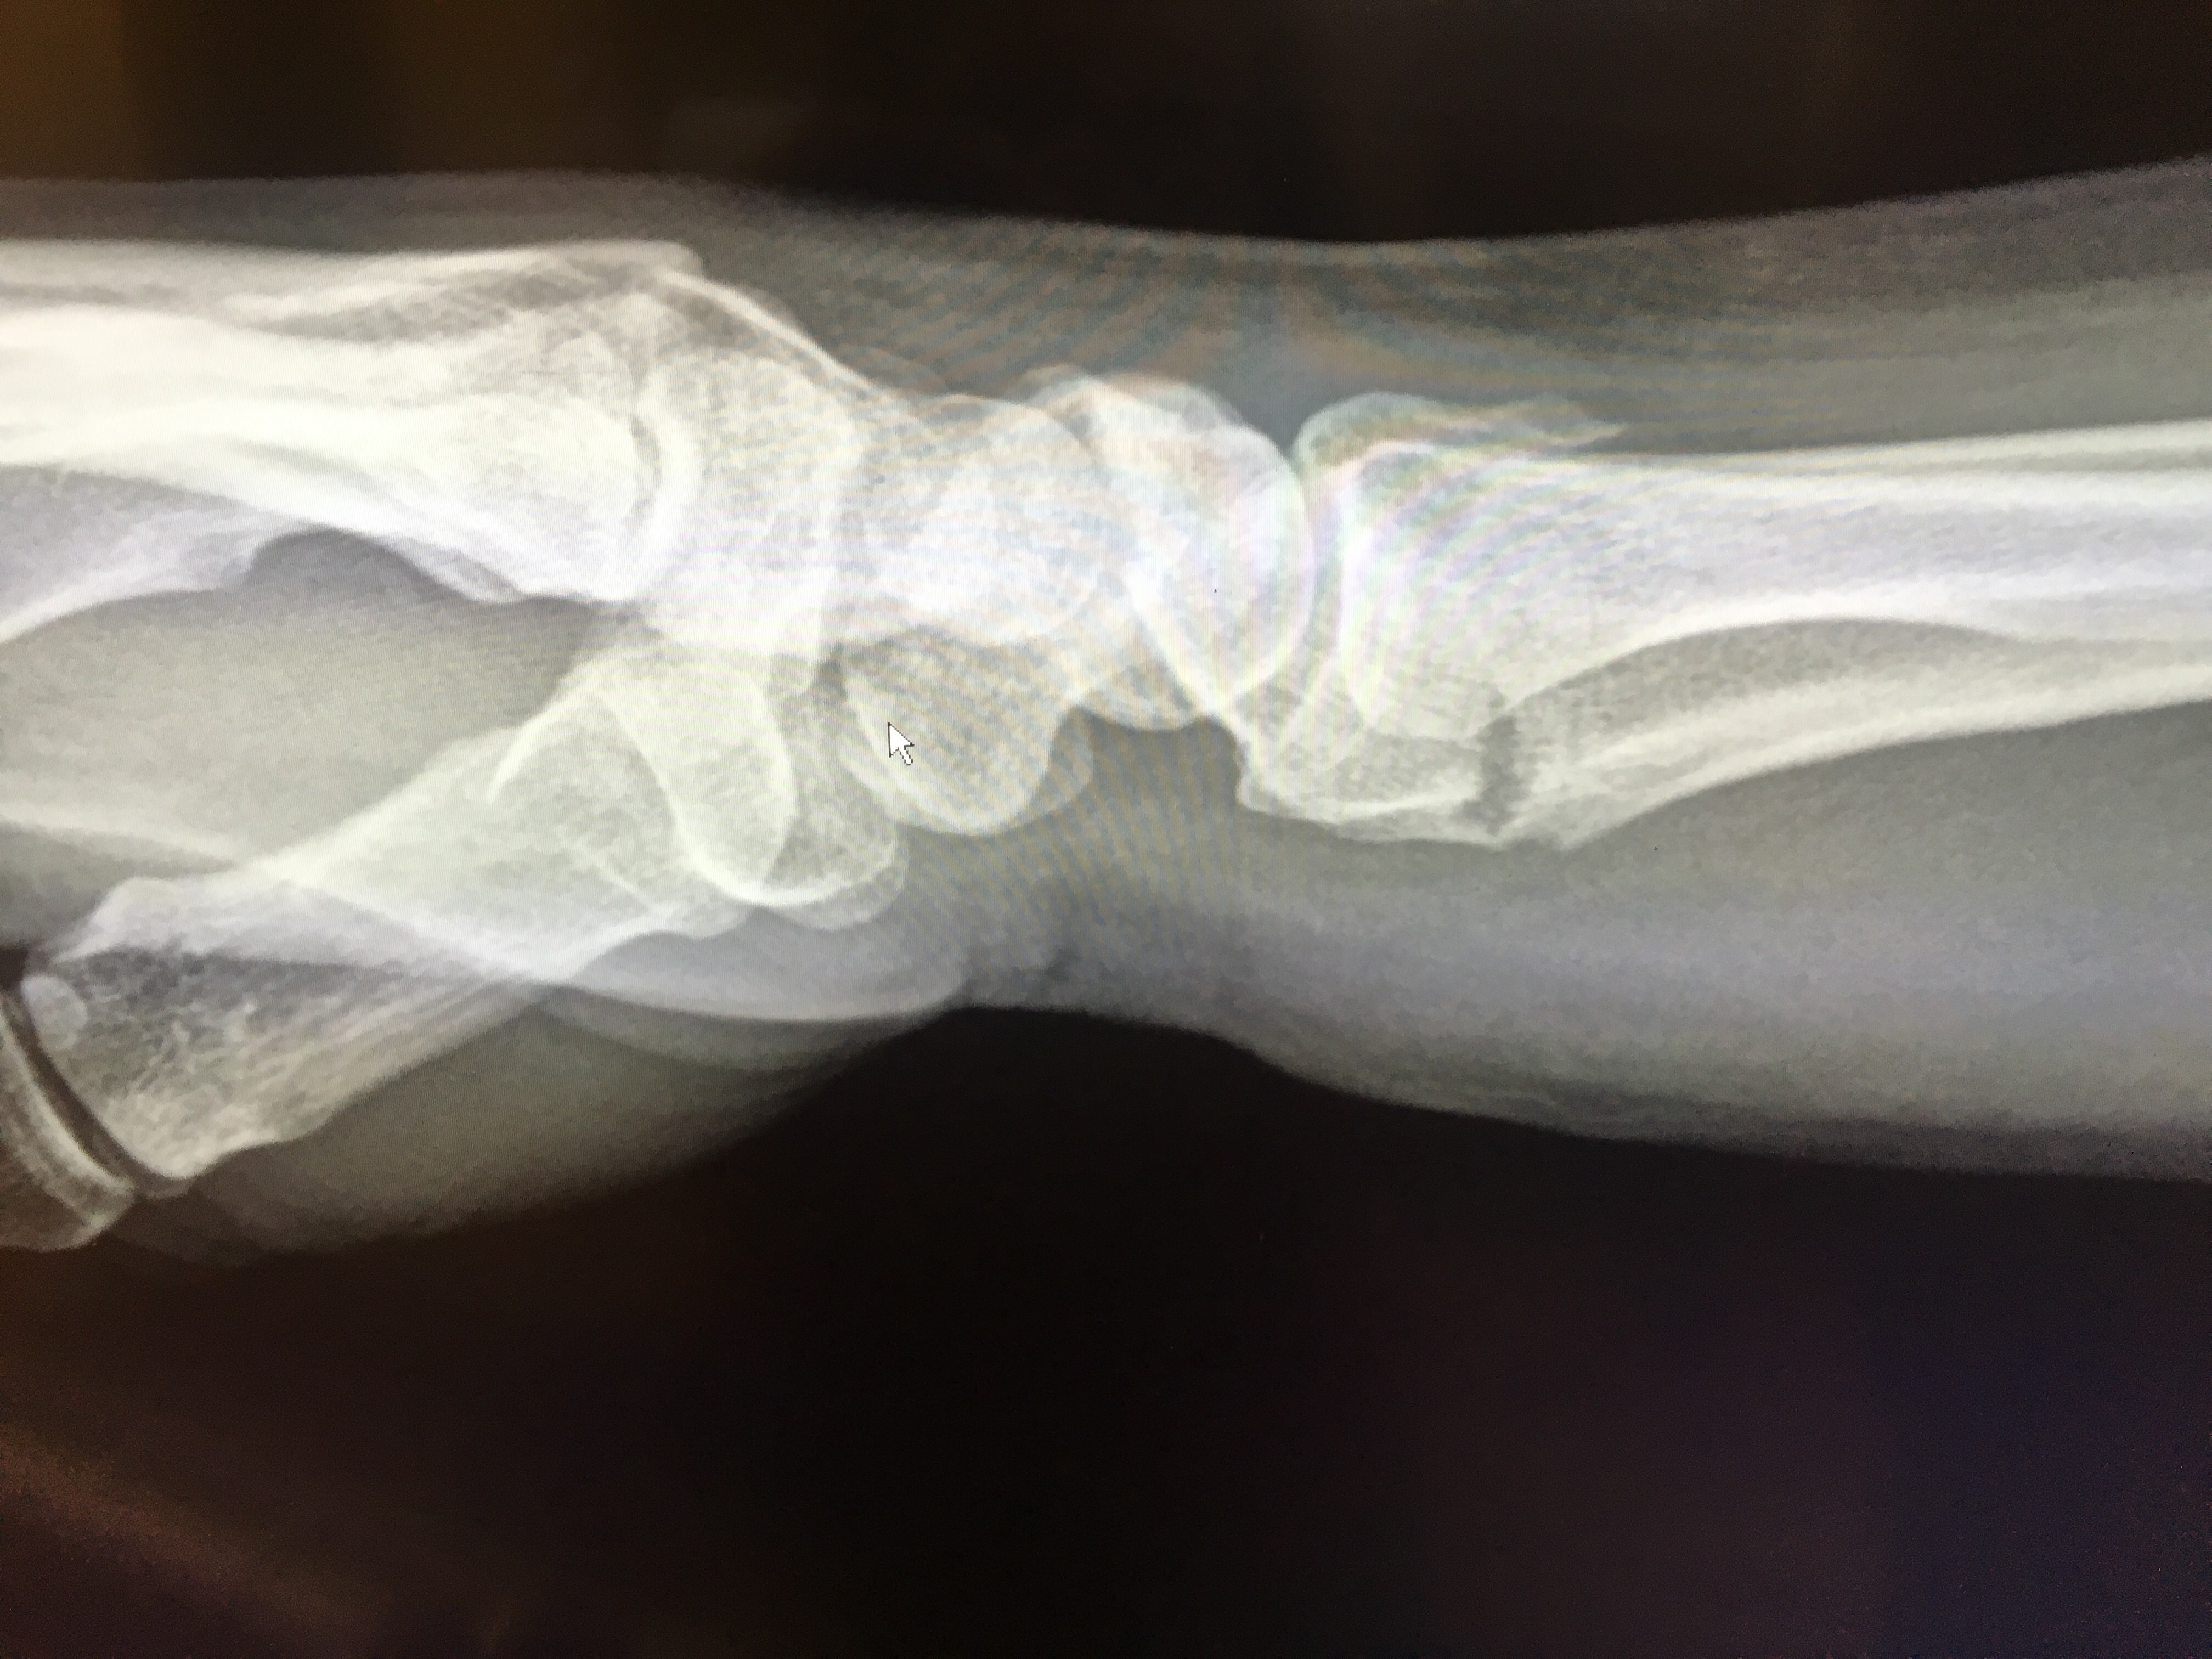

Things have since taken a bit of a sad turn. The orthopedic surgeon wanted to do surgery (today), planning to insert a plate so as to realign the displaced radial bone in my wrist.

But my travel insurance company are insisting that I return to Australia for treatment. So my wrist is in a temporary splint, my AT thru hike is on hiatus and instead of R&R for the recent injury, I have to embark on a 24 hour series of flights with a backpack that I can’t currently lift. Hmmm. Yay?